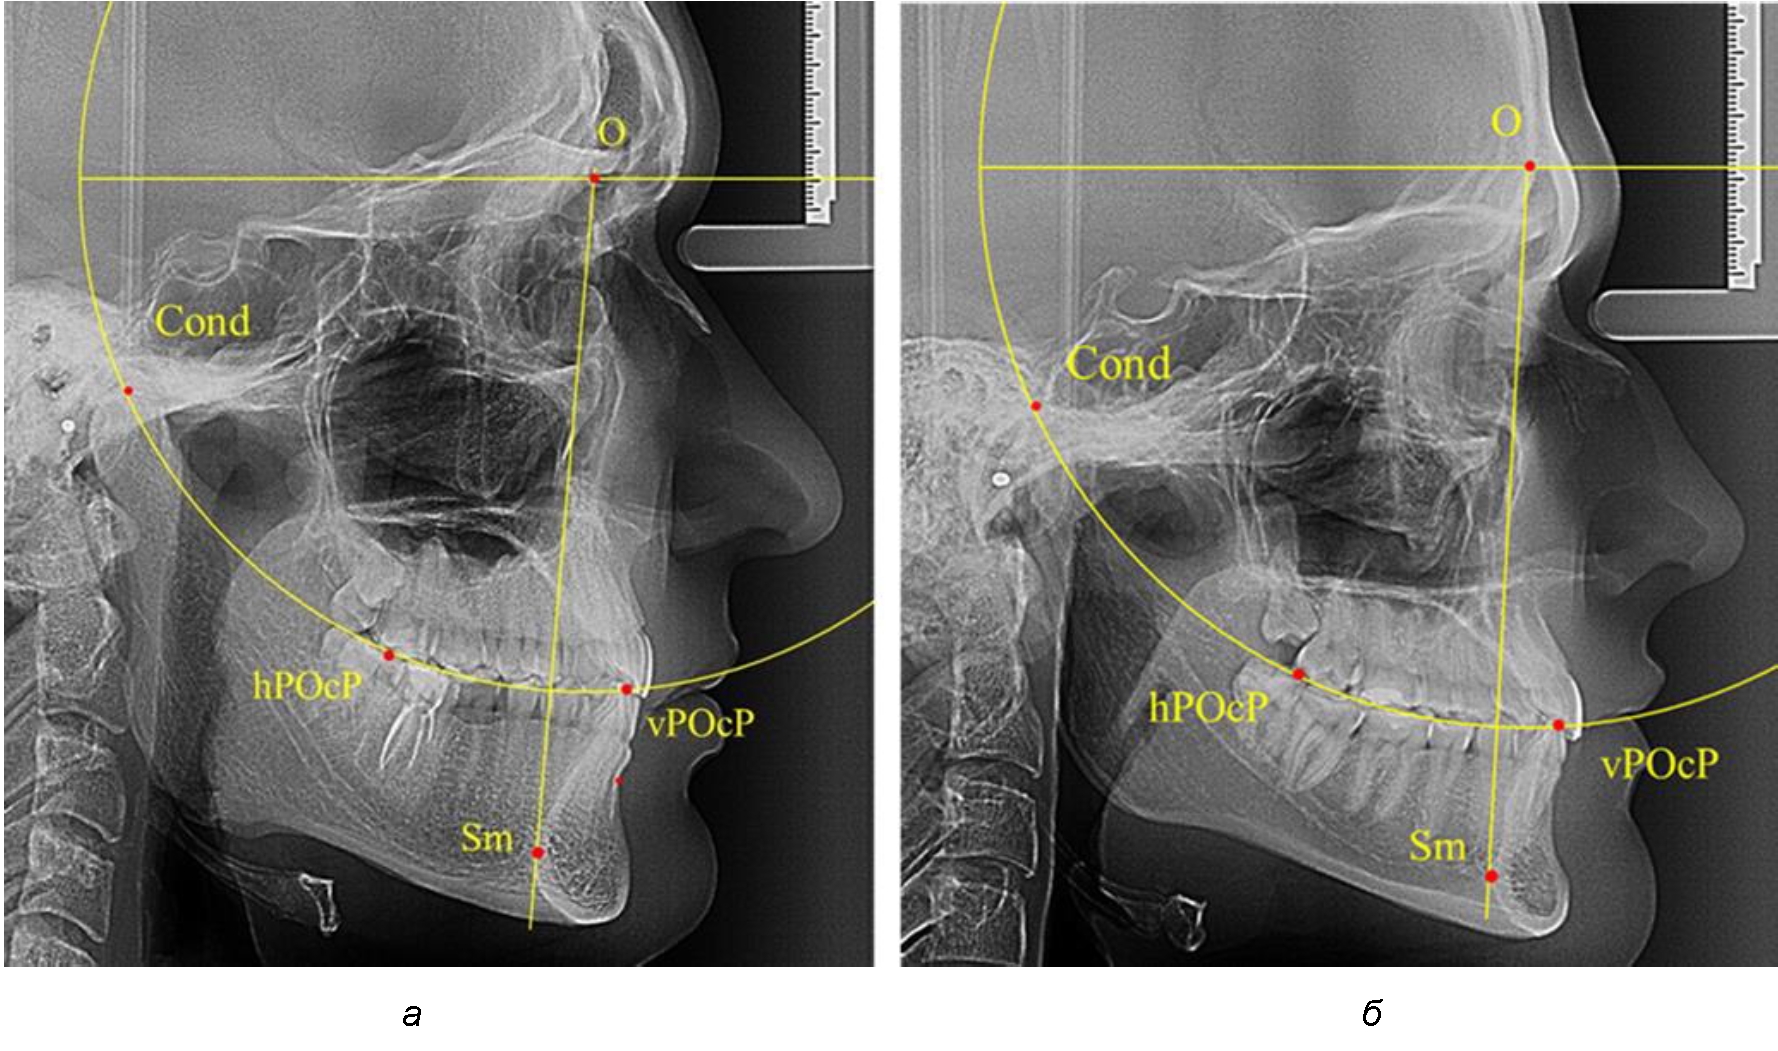

Анализ снимков проводили с использованием традиционного построения стресс-оси по Bimler. Для удобства построения использовали компьютерную программу PowerPoint. Основными точками для построения круга были передняя (vPOcP) и дистальная (hPOcP) окклюзионные точки, а также верхняя выпуклость суставной головки (Cond).

Вставка из программы в виде овала накладывалась на фотографию рентгенограммы и ручным способом растягивалась так, чтобы получился круг, проходящий через обозначенные реперные точки.

Центр окружности О, соединяющей точку резцового перекрытия с жевательной поверхностью зубов и серединой суставных головок, соединяли с выступающей точкой Sm на внутреннем контуре подбородка (рис. 1).

Рис. 1. Метод анализа ТРГ по Bimler

В норме, по резульатам исследования автора, линия Bimler проходила по вертикальной оси первых премоляров, что мы также расценивали как оптимальное их расположение.

Результаты исследования рентгенограмм с мезотрузионным типом резцов показали, что линия Bimler проходила позади первых премоляров у людей с широким типом подбородочного выступа, однако окклюзия была физиологической и не требовала удаления премоляров, что носило рекомендательный характер при проведении подобных исследований при аномалиях прикуса. У людей со средними формами подбородочного выступа линия Bimler проходила впереди первых премоляров (рис. 2).

Аналогичная ситуация была у людей и с узкими вариантами подбородочного выступа.

Таким образом, при мезотрузионном типе зубочелюстных дуг расположение премоляра впереди линии Bimler при широких вариантах подбородка не может быть критерием выбора экстракционных методов лечения.

Рис. 2. Положение первых верхних премоляров при мезотрузии с широкими (а) и средними (б) размерами подбородка